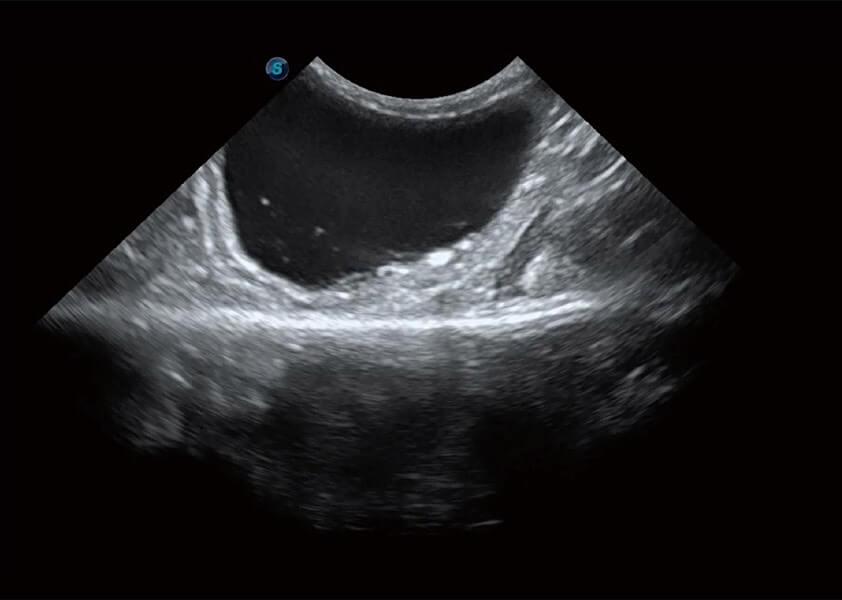

ProPet 60 作为一款高端台式动物超声设备,为动物医生的日常诊断提供了一系列贴合动物临床需求、解决临床实际问题的高级成像功能。凭借全系列高清探头,满足医生对腹部、心脏、生殖、浅表、肌骨等成像的所有需求,切实帮助您提升检查效率,提高诊断信心。

兽用彩色多普勒超声诊断系统